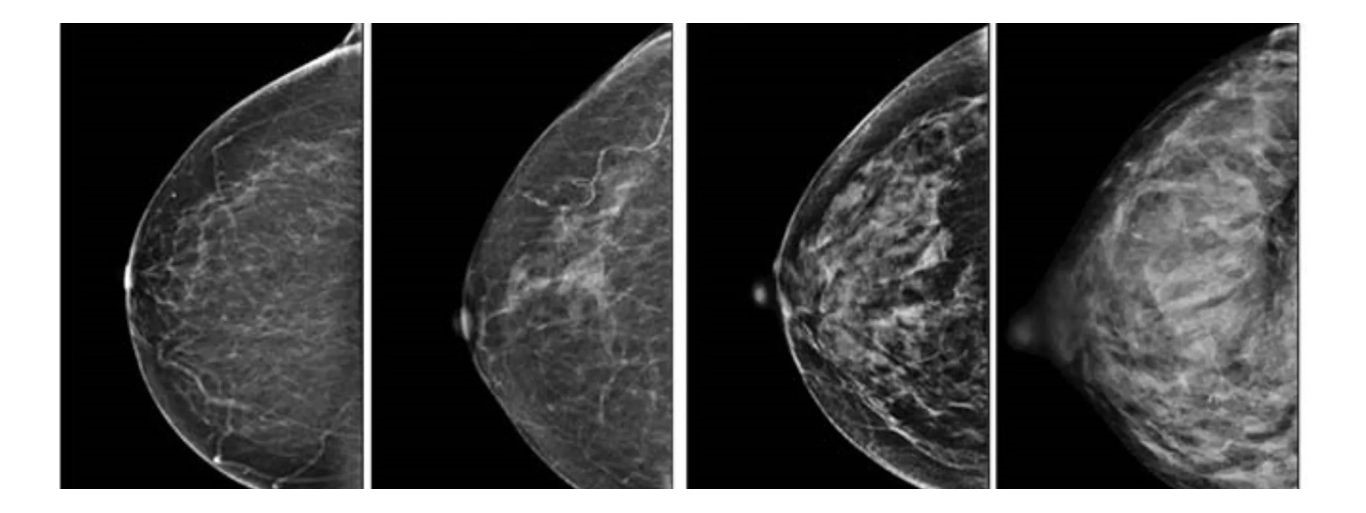

Snímky z mamografu

Mamografie je radiologická metoda vyšetřování prsu (rentgenové vyšetření). Využívá rentgenové paprsky k vytvoření obrazů vnitřních struktur těla. Na snímcích se hodnotí řada detailů, které mohou napovědět, zda se jedná o normální nález, nebo o něco, co vyžaduje další vyšetření:

Mikrokalcifikace – drobné bílé tečky, které mohou být projevem neškodných změn, ale také jedním z prvních znaků karcinomu.

Ložiskové útvary – na snímku se zobrazují jako stíny či zhuštěná oblast tkáně. Důležitý je jejich tvar a okraje – pravidelný, hladký útvar většinou značí benigní proces, nepravidelné a hvězdicovité okraje spíše budí podezření.

Asymetrie – porovnává se pravý a levý prs, případně aktuální snímek s těmi staršími. Nově vzniklá odchylka je vždy důvodem k bližšímu zkoumání.